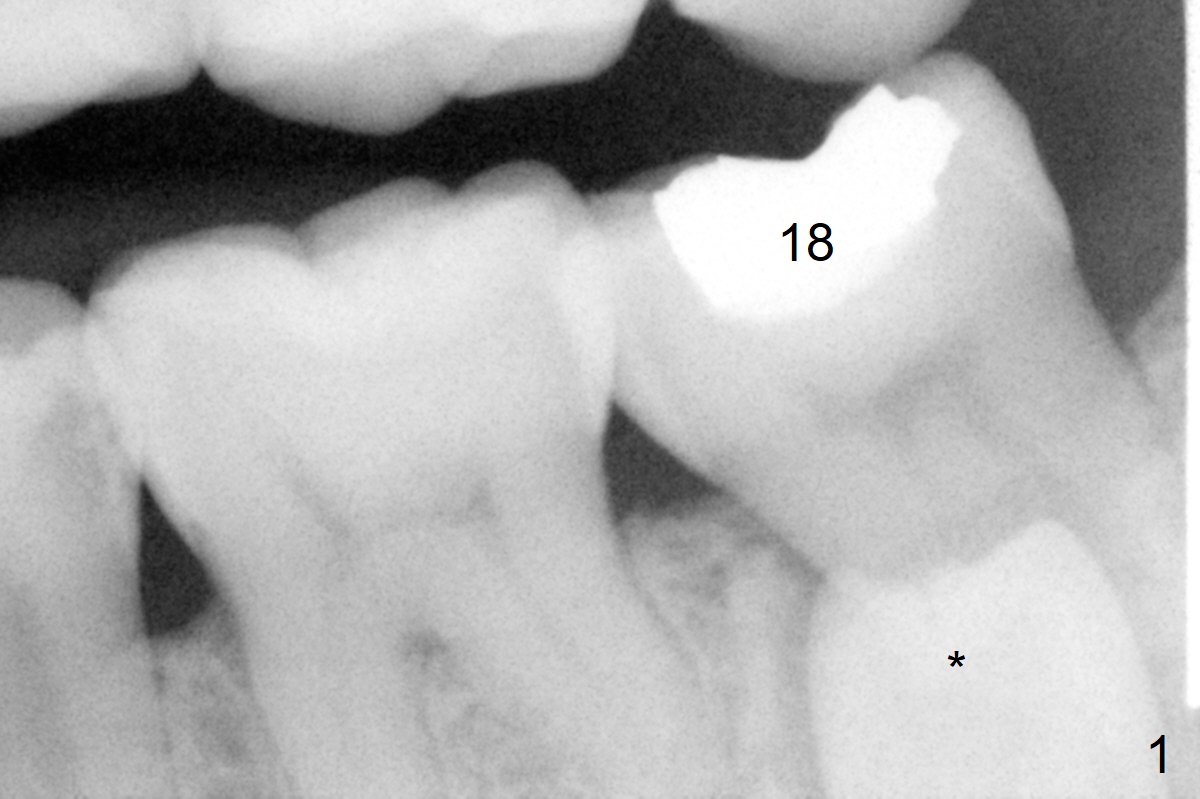

A 45-year-old woman with severe crowding (Fig.2) presented to my office 9 years ago; the tooth #18 appears to have root resorption, most likely due to a supernumerary tooth (Fig.1 *).  The latter seems to be erupting in 6 and 9 years (Fig.2,3), probably because of immature apex (Fig.2, as compared to the supernumerary tooth in the lower right (*)).  Recently the patient has transient sensitivity at #18.  The tooth has mobility I without deep periodontal pockets.  If the tooth #18 turns to be non-salvageable, what should be done?  The tooth #20 has received root canal therapy, while the tooth #29 has had RCT retreat.